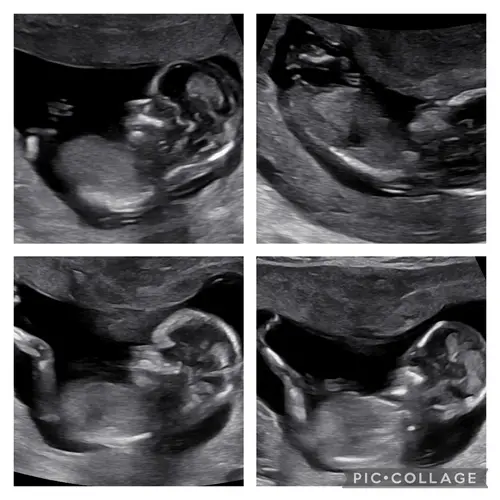

Iemand een idee? In de vorige topic 2x meisje 1x een jongentje werd er gezegd maar vandaag een nieuwe echo gehad bij de 13.4 weken vandaar nogmaals de vraag 😊

Reactie op Wensmoeder0546

Iemand een idee? In de vorige topic 2x meisje 1x een jongentje werd er geze ...

Geen nub te zien

Kan je toevallig hierin wel wat zien haha?

Deze had je keertje al geposted hihi, ik denk wel jongen

Ah oké! Deze foto’s waren met 13+2